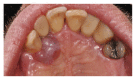

Purpose. Implant therapy plays an important role in contemporary dentistry with high rates of long-term success. However, in recent years, the incidence of peri-implantitis and implant failures has significantly increased. The peripheral giant cell granuloma (PGCG) rarely occurs in peri-implant tissues and it is clinically comparable to the lesions associated with natural teeth. Therefore, the study of possible diseases associated with dental implants plays an important role in order to be able to diagnose and treat these conditions. Materials and Methods. This report described a 60-year-old Caucasian male who presented a reddish-purple pedunculated mass, of about 2 cm in diameter, associated with a dental implant and the adjacent natural tooth. Results. An excisional biopsy was performed and the dental implant was not removed. Histological examination provided the diagnosis of PGCG. After 19-month follow-up, there were no signs of recurrence of peri-implantitis around the implant. Conclusion. The correct diagnosis and appropriate surgical treatment of peri-implant giant cell granuloma are very important for a proper management of the lesion in order to preserve the implant prosthetic rehabilitation and prevent recurrences.